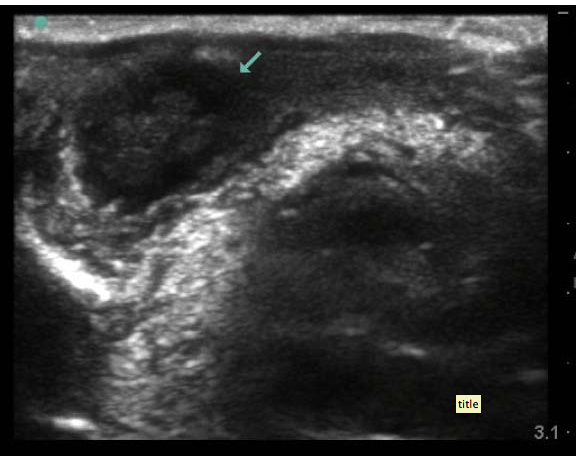

“41-year-old male who presents to the ED with concerns that his left eye is progressively getting more swollen. He’s had some increasing eye pain and purulent drainage over the past six days. At first he thought that he was just having really bad seasonal allergies, but today, he started feeling a “pulling sensation” on the medial aspect of his left eye. He denies any headache, diplopia, sinus pain, rhinorrhea, nausea, vomiting, or recent trauma. He does note a subjective fever at home, and his temperature is 38.2°C in the ED. His vital signs otherwise demonstrate tachycardia to 123 bpm, but a normal blood pressure, oxygen saturation, and respiratory rate. Your intern has asked the nurse to obtain a visual acuity on the patient and he is systematically going through his ocular exam when you walk by the room to check on him. He comes out of the room to give you an update on what he’s discovered so far. The patient has tenderness to palpation over his left medial orbit and possible entrapment on ocular exam. He has no additional pain with extraocular movement and no diplopia, but has so much periorbital edema that it wasn’t possible to get a consistent Tonopen measurement. There doesn’t appear to be any fluorescein uptake on the slit lamp exam, and other than conjunctival injection and the lid swelling, the patient has a normal ocular exam.

It is now about 4:30 pm and you know that in 30 minutes, all consultants turn into pumpkins and their pagers magically stop working. As you are about to ask your intern what he wants to do next, the medical student pulls up the ultrasound machine that the intern asked her to wheel over and hands it to him. He takes the linear array transducer and performs an ocular ultrasound at the bedside. He saves the following images: what do you see?”

Screen shot 2013-01-07 at 1.57.22 PM